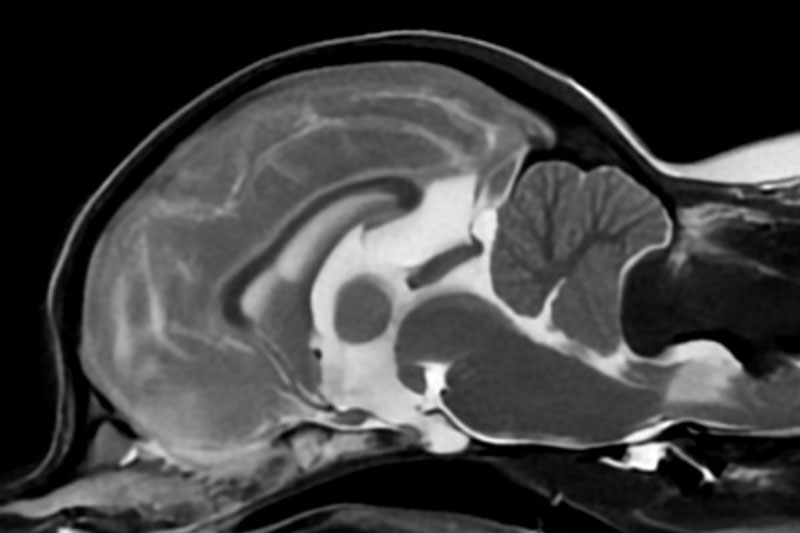

본 병원은 GE사의 1.5T 고해상도 자기공명영상장치(MRI)를 이용하여, 자기장을 이용한 비침습적 방식으로 뇌, 척수, 근골격계 등 다양한 연부조직을 정밀하게 영상화할 수 있습니다. MRI는 방사선을 사용하지 않아 반복 촬영에도 안전하며, 신경계 및 연부조직에 대한 탁월한 해상도를 제공하여 정확한 진단에 매우 유용합니다.

또한 본원의 MRI 장비는 GE사의 PROPELLER 기법을 도입하여 호흡이나 움직임에 따른 영상 왜곡을 최소화하면서도 검사 시간을 단축시켜, AI 기반 영상 처리 기술을 통해 노이즈를 줄이고 더욱 선명하고 명확한 영상을 획득할 수 있습니다. 이러한 기술적 강점을 바탕으로 마취 시간과 그에 따른 환자의 부담을 줄이면서도, 진단에 충분한 고화질 영상을 안정적으로 확보할 수 있습니다.

| 뇌/두개강 | 뇌종양, 뇌염, 수두증, 간질, 뇌출혈, 시신경 이상 등 |